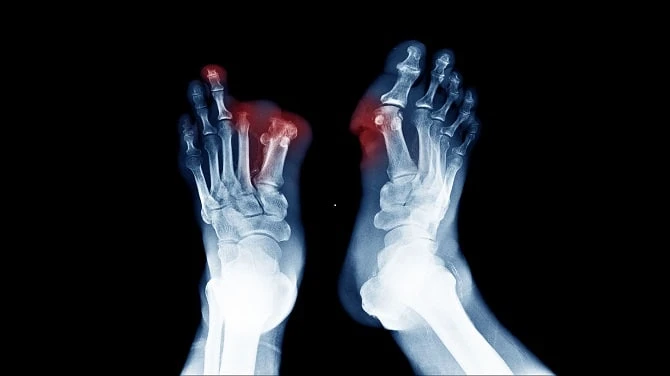

When your peripheral nervous system is injured, you have peripheral neuropathy. The information from your brain and spinal cord (central nervous system) is sent to the rest of your body via your peripheral nervous system. Peripheral neuropathy can be caused by accidents, infections, or exposure to toxins, but it is most usually caused by diabetes. Diabetic neuropathy is the term used in this scenario.

There is no recognized cure for diabetic neuropathy. Slowing the development of the illness, reducing discomfort, controlling complications, and, when feasible, regaining function are the only aims of treatment for DN. Anti-seizure medicines for nerve pain and antidepressants for pain relief are among the current treatments.

Neurotrophic (related to nerve tissue growth) or angiogenic (related to new blood vessel production) substances must be added to effectively treat DN. MSCs produce neurotrophic factors, angiogenic factors, cytokines, and immunomodulatory substances paracrinely (cell-to-cell communication) to alleviate symptoms and decrease the course of diabetic neuropathy.